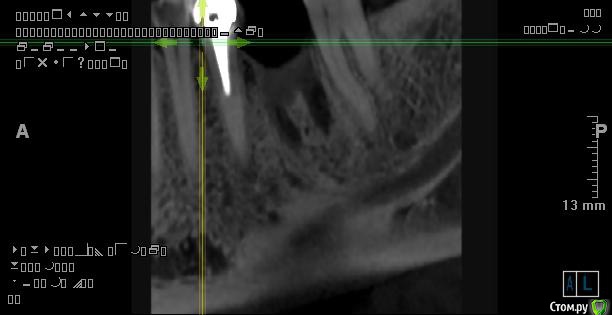

Самарец Опубликовано 11 августа, 2020 Автор Поделиться Опубликовано 11 августа, 2020 срезы выставлены не корректно, покажите еще, в том числе в области седьмого зубаСпасибо за ответ. Так пойдёт? Ссылка на комментарий

Irouil Опубликовано 11 августа, 2020 Поделиться Опубликовано 11 августа, 2020 Все в порядке 1 Ссылка на комментарий